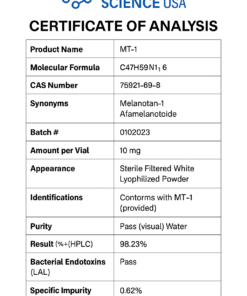

MS Adipotide (FTPP) Certificate